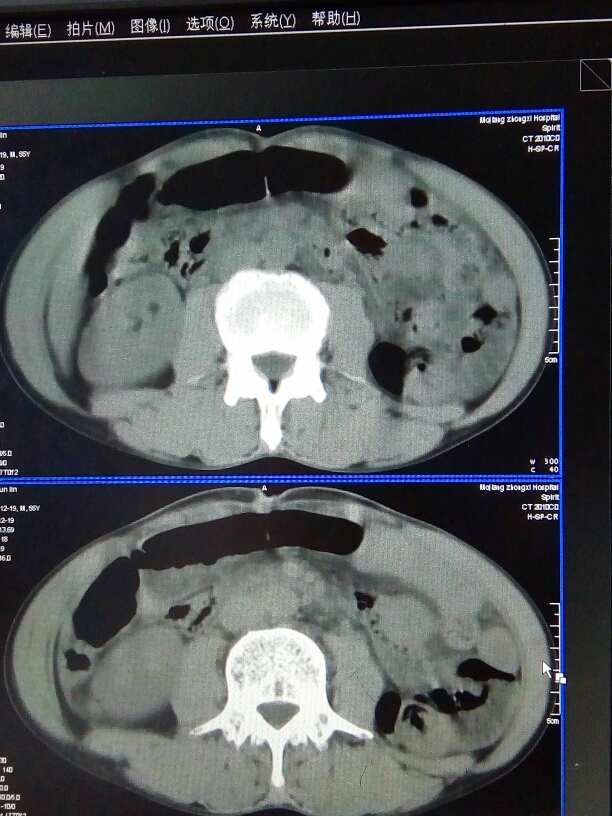

CT52477:下腹部

盆腔宽大液平面。

盆腔内可见多个囊实性病变,幷见宽大液平,病灶周围见多发气体密度影,盆腔积液。腹盆腔肠管脂肪间隙模糊。腹主动脉旁见软组织密度结节。考虑:盆腔脓肿。

盆腔脓肿伴蜂窝织炎可能性大

盆腔脓肿考虑可能大